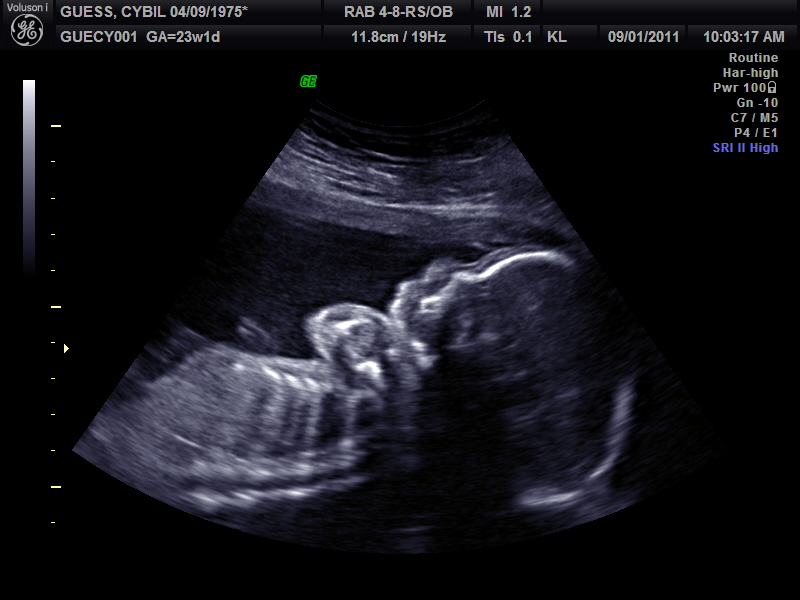

We had our sonogram on Thursday and here are some pictures of the little one!

Profile.  The baby was moving a lot and this picture

caught a double exposure. There are not 2 babies!